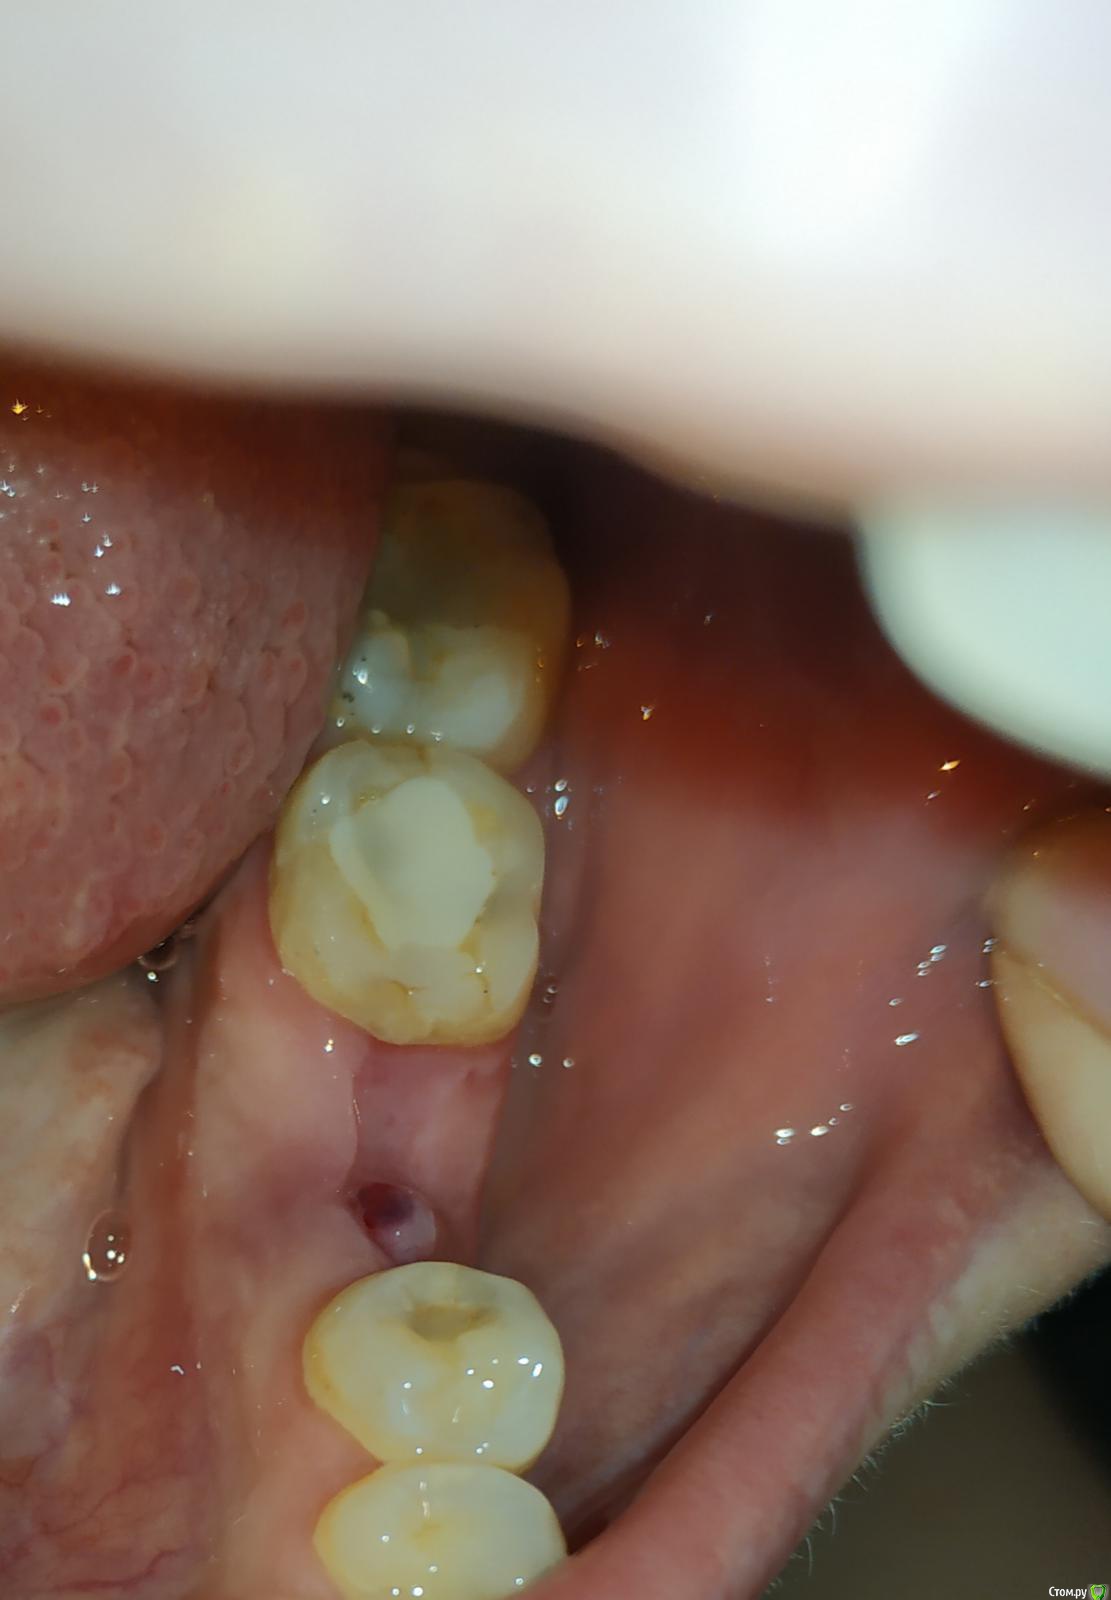

Jammy Опубликовано 22 октября, 2019 Поделиться Опубликовано 22 октября, 2019 (изменено) Доброго времени суток! 11 сентября удалили зуб, лунка заживала хорошо до недавнего времени. Вчера обнаружила странное образование в части лунки, чуть отличающееся по цвету от остальной десны.Выслала фото стоматологу, который удалял зуб, он сказал чтобы я не волновалась-это складка слизистой. Сегодня на этой складке появилось подкожное кровяное пятно. Стоит ли обращаться к врачу или это норма? Не сталкивалась ранее с процесс ом заживление лунки, оттого волнуюсь.Прошу прощения за качество фото (снимки сделаны вчера и сегодня) спасибо Изменено 22 октября, 2019 пользователем Jammy Ссылка на комментарий

Jammy Опубликовано 23 октября, 2019 Автор Поделиться Опубликовано 23 октября, 2019 покажитесьСпасибо за совет! сходила к стоматологу - терапевту, но мне сказали, что нужно записываться к стоматологу - хирургу..на снимок отправили- ничего на нем не обнаружено. У хирурга ещё не была, но терапевт упомянула слово грануляция и сказала, возможно потребуется чистка. Ссылка на комментарий

dentikl Опубликовано 24 октября, 2019 Поделиться Опубликовано 24 октября, 2019 Спасибо за совет! сходила к стоматологу - терапевту, но мне сказали, что нужно записываться к стоматологу - хирургу..на снимок отправили- ничего на нем не обнаружено. У хирурга ещё не была, но терапевт упомянула слово грануляция и сказала, возможно потребуется чистка.да, было видно на Вашем фото Ссылка на комментарий